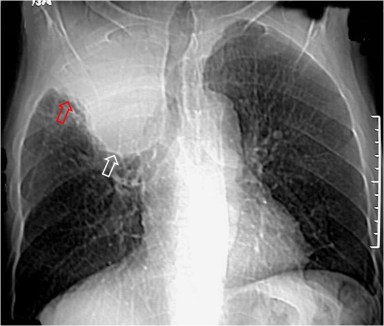

SIGNO DE LUFTSICHEL

Signo de colapso del lóbulo superior izquierdo en la radiografía posteroanterior de tórax. Consiste en la hiperclaridad o lámina aérea alrededor del arco aórtico (flechas) producida por la hiperinsuflación del lóbulo inferior izquierdo, que asciende hasta el vértice pulmonar. El segmento 6 contacta con la parte posterior del botón aórtico, permitiendo que éste sea visualizado con gran nitidez.

El nombre del signo corresponde a los términos germanos luft (aire) y sichel (hoz).

La proyección lateral confirma el colapso del lóbulo superior izquierdo, manifestado por el aumento de densidad anterosuperior, el desplazamiento anterior de la cisura mayor y la hiperinsuflación del lóbulo inferior.